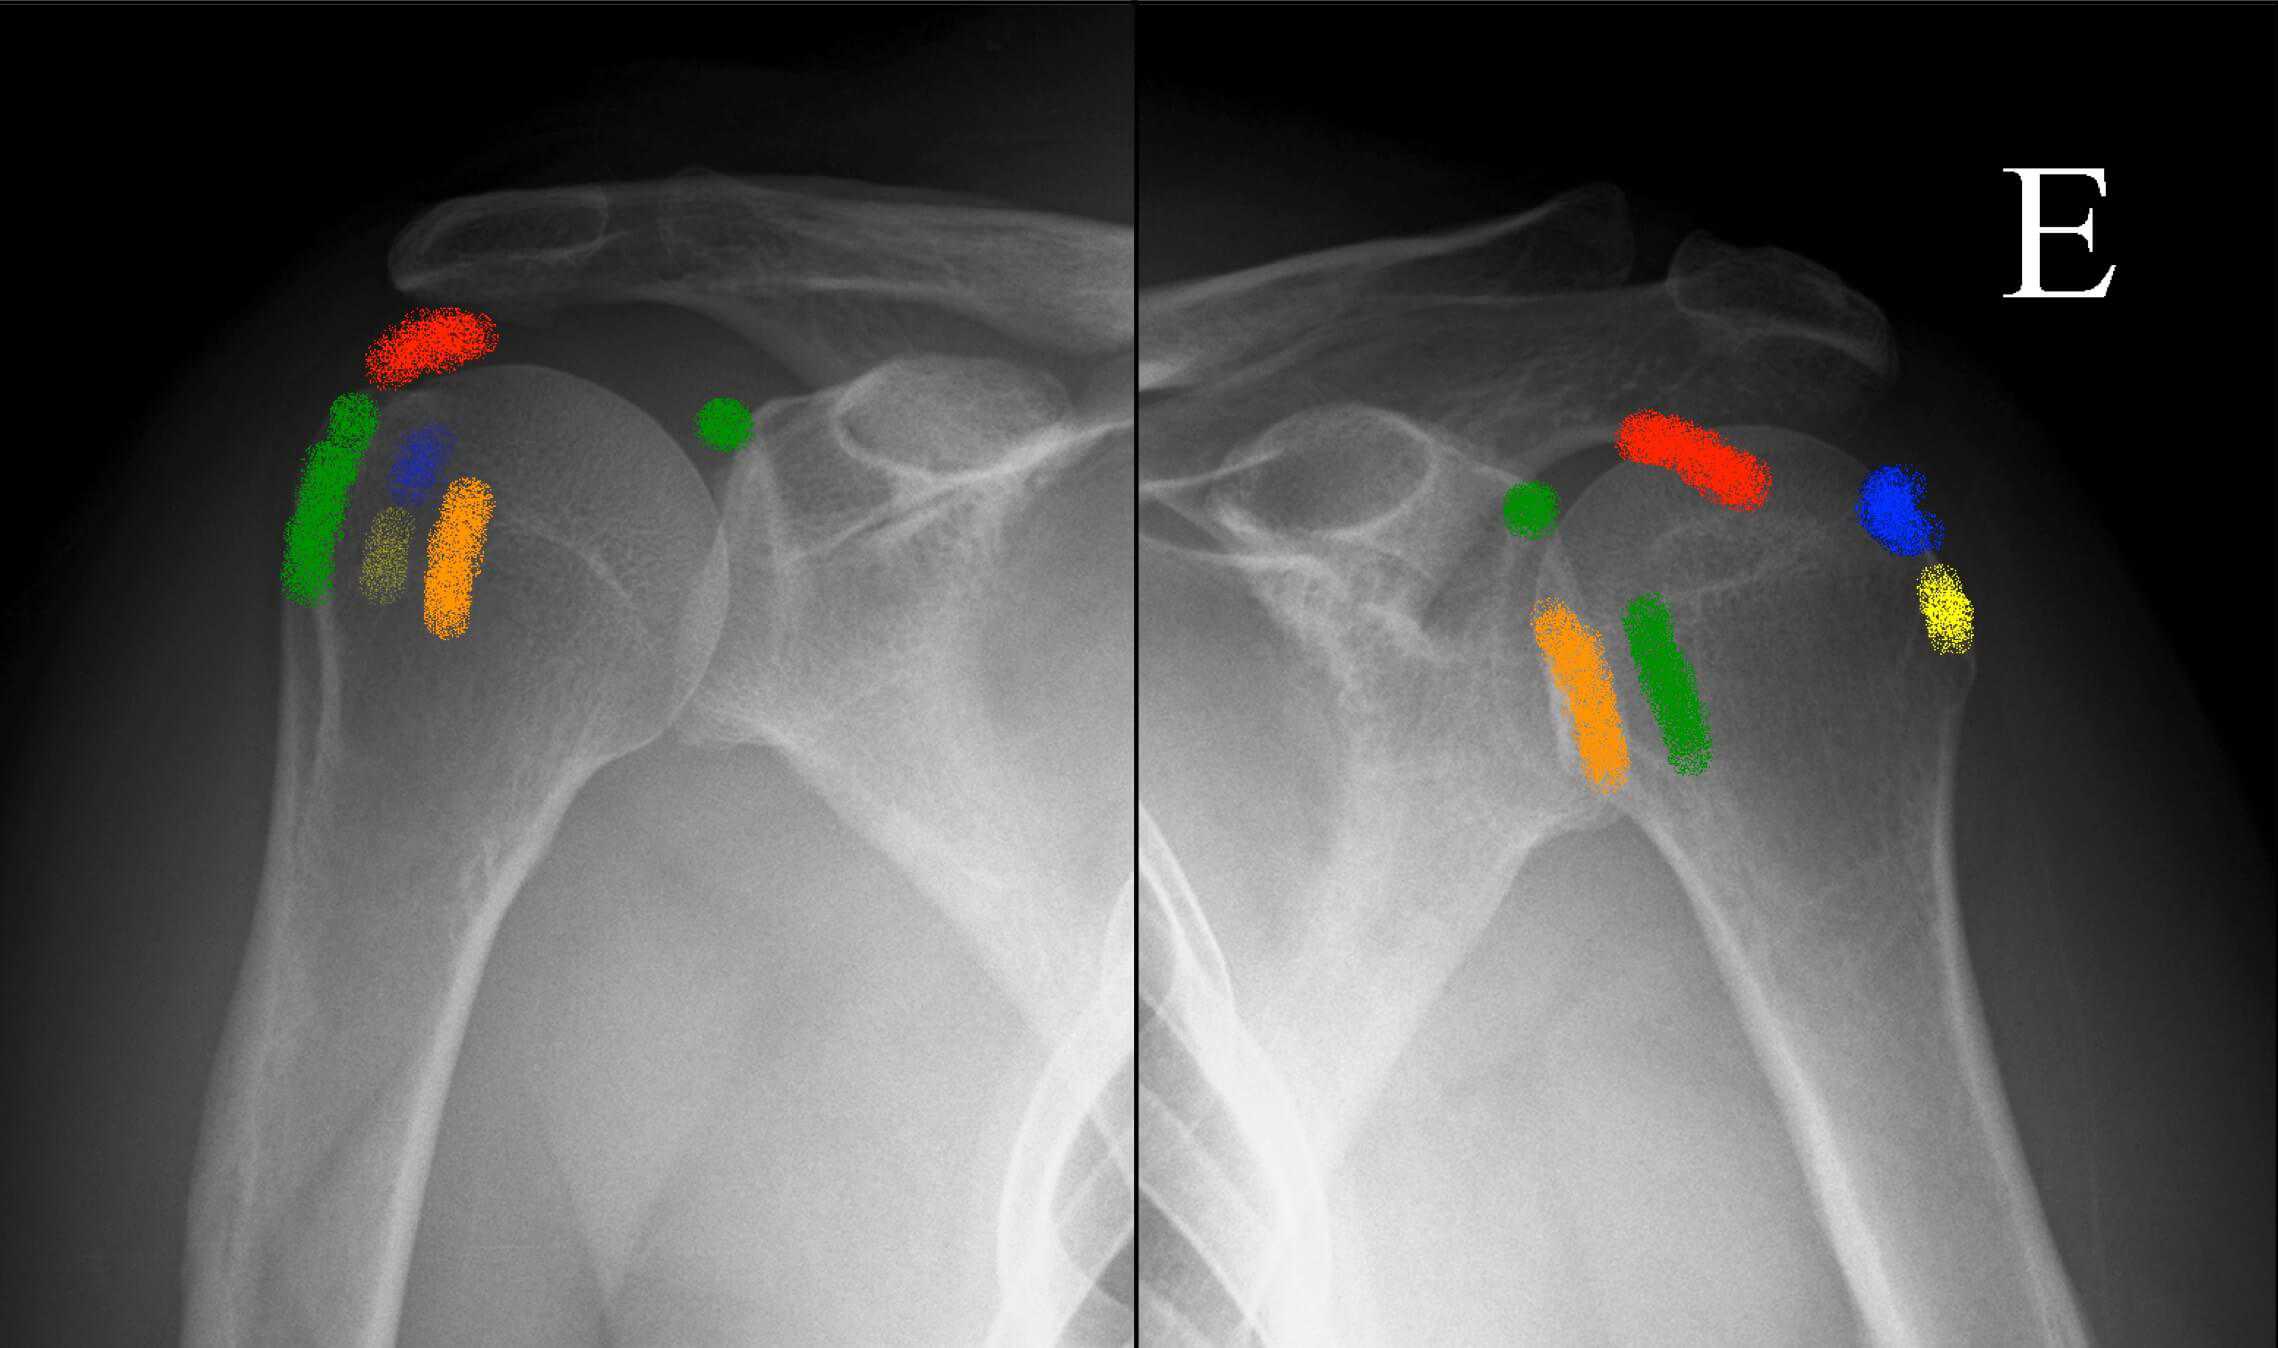

🖼 Hình 1 – Phân bố giải phẫu vôi hóa gân chóp xoay

AP X-quang vai: gân trên gai (mũi tên dài), gân dưới gai (mũi tên ngắn), gân dưới đòn (đầu mũi tên)

Phân bố giải phẫu vôi hóa gân chóp xoay

3.2 Phân loại X-quang theo Gärtner & Heyer

Phân loại này dựa trên hình thái học trên X-quang và tương quan với giai đoạn bệnh học. Đây là công cụ tiên lượng quan trọng trong lựa chọn điều trị:

LoạiHình thái X-quangCấu trúc vôiGiai đoạn tương ứngTiên lượng

Type I Đậm đặc, đồng nhất, bờ rõ (dense, homogeneous) Canxi dạng hạt thô – rắn chắc (formative) Pha tạo thành / nghỉ Khó hút qua kim; ưu tiên ESWT

Type II Không thể phân loại rõ ràng vào I hoặc III Trung gian Chuyển tiếp Đáp ứng biến thiên

Type III Mờ, không đồng nhất, bờ không rõ (fluffy, translucent) Canxi dạng huyền phù sữa – lỏng (resorptive) Pha tiêu hủy Dễ hút qua kim; barbotage hiệu quả cao

Ý nghĩa lâm sàng: Gärtner Type I (rắn) → kết quả hút kém, ưu tiên ESWT hoặc phẫu thuật. Gärtner Type III (lỏng) → dễ hút qua barbotage, hiệu quả cao nhất khi đau cấp tính.

🖼 Hình 4 – Phân loại Gärtner trên X-quang

Type I: bờ đậm rõ | Type II: trung gian | Type III: mờ, bờ không rõ

Phân loại Gärtner trên X-quang